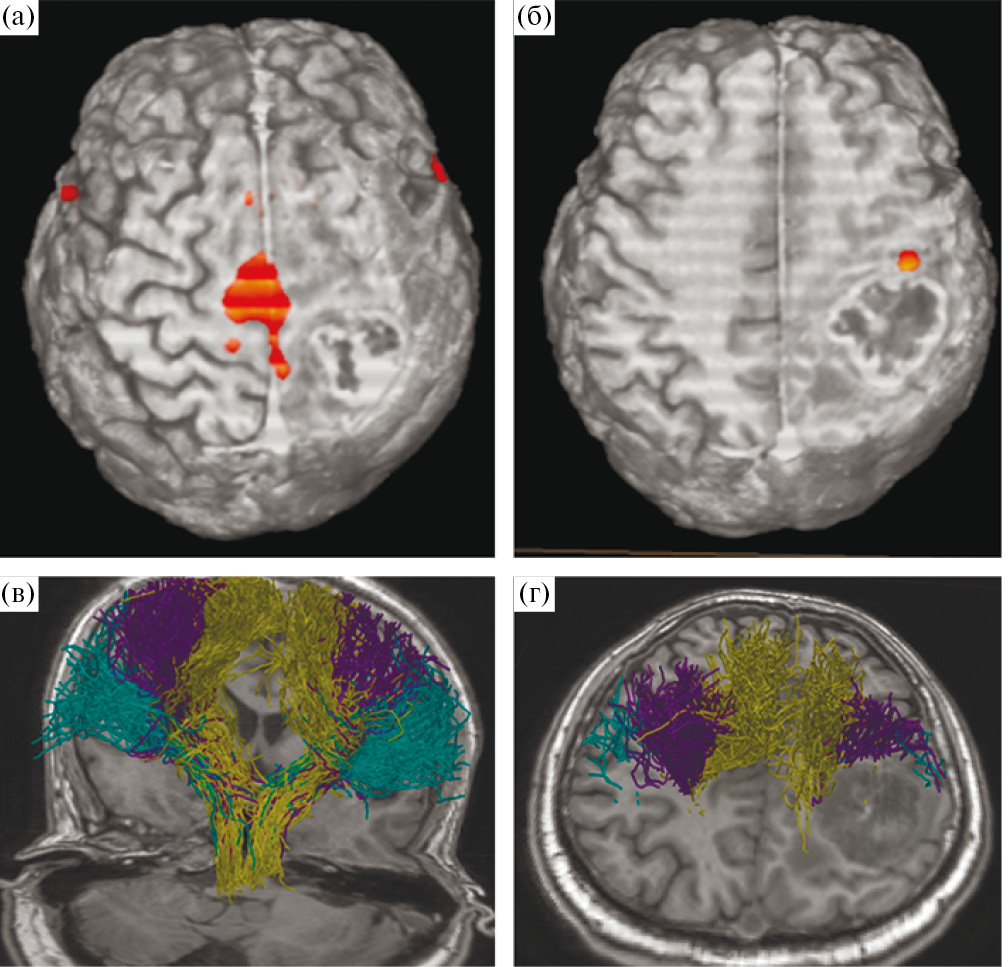

Учитывая локализацию процесса и клиническую картину заболевания, в качестве предоперационной подготовки пациенту были проведены фМРТ с визуализацией моторных зон и МР-трактография с построением КСТ (рис. 4).

Рис. 4. МРТ у пациента с внутримозговой опухолью правой теменной доли. (а, б) – данные фМРТ; (а) – оранжевым цветом обозначена корковая зона ноги, располагающаяся вовнутрь и на некотором отдалении от медиальной границы опухоли; (б) – представлена зона руки, прилегающая к переднему краю опухоли; (в, г) – данные МР-трактографии (CSD HARDI), использованный алгоритм построения позволил построить и разделить волокна КСТ, иннервирующие ногу (горчичный цвет), руку (фиолетовый), лицо (зеленый). Волокна КСТ прилегают к медиальному и переднему краям опухоли.

Fig. 4. fMRI (leg and arm areas) and MR-tractography (CSD HARDI, yellow – leg, purple – hand, green – facial muscles) before surgery.

В связи с непосредственной близостью опухоли к моторным центрам головного мозга запланировано проведение операции с обязательным нейрофизиологическим мониторингом, включающим динамику ТК МВП, прямую кортикальную и субкортикальную монои биполярную стимуляции и использование магнитной интраоперационной навигационной системы FIAGON. Для использования последней данные фМРТ, МР-трактографии и структурной МРТ были корегистрированы в едином файле. Для демаркации границ опухоли также использовалась флуоресцентная навигация (препарат «Аласенс»). Опухолевая ткань светилась ярко-розовым цветом.